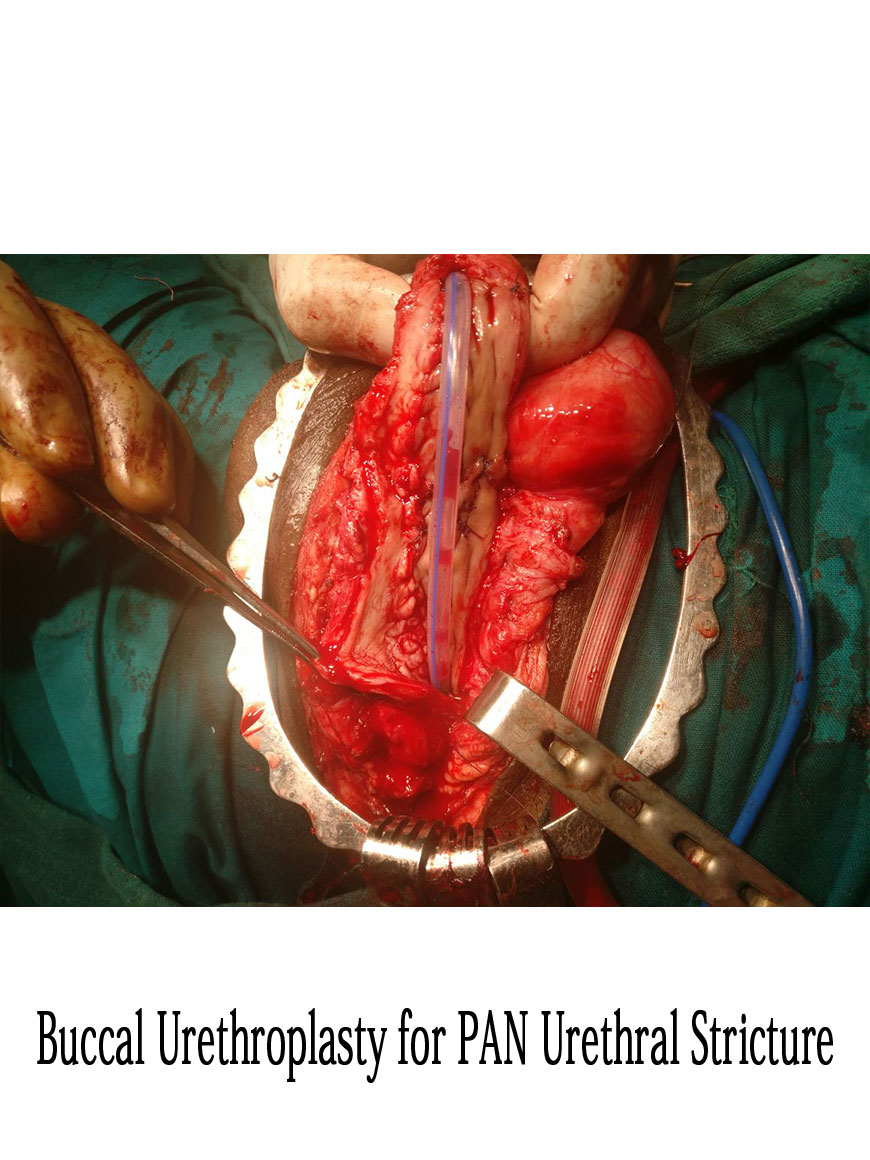

Buccal Urethroplasty for Pan Urethral Stricture